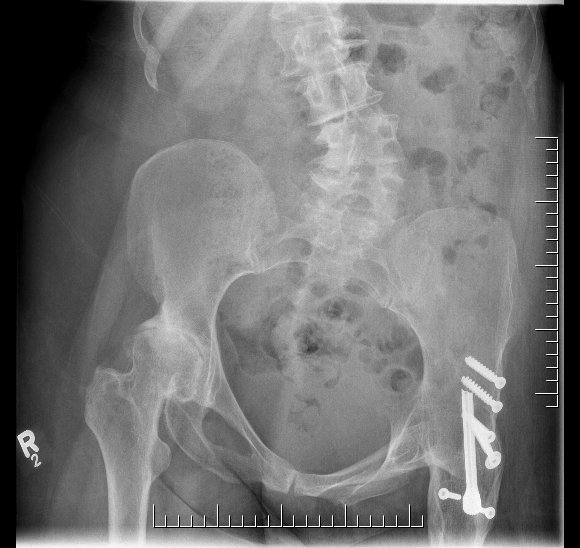

Identification of acetabulum and restoration of anatomical hip center

- normal landmarks not identifiable

- need to establish correct position and depth

- have to ream away femoral head

- consider image less navigation / CT guidance / robotic guidance

Restoration of leg length

- maximum 4cm lengthening